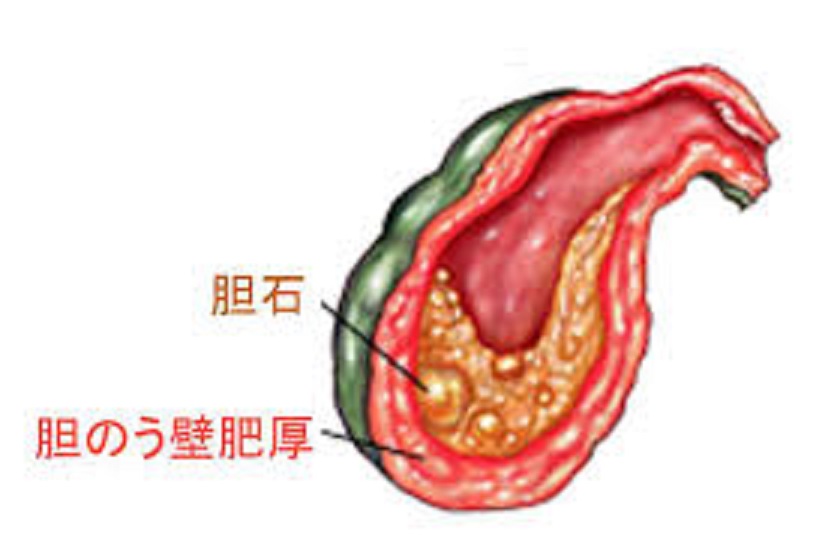

データは非常に単純かつ直接的です。結石、つまり有名なによる胆管閉塞のケースの実質 90% は最終的に胆嚢炎 (この場合は結石性胆嚢炎と呼ばれます) を引き起こします。

胆石は、胆汁物質の生成や濃度の変化、および/またはコレステロールを増加させる脂肪分の多い食品の過剰摂取による胆汁物質の硬化によって形成されます。そして、この状態は無症状であることがほとんどです。

胆嚢が閉塞すると、炎症を起こすまで収縮して正常に空にすることができません。最初の症状は腹痛であり、腹痛が激化し、吐き気や嘔吐も引き起こします。発熱はある場合もあれば、ない場合もあります。